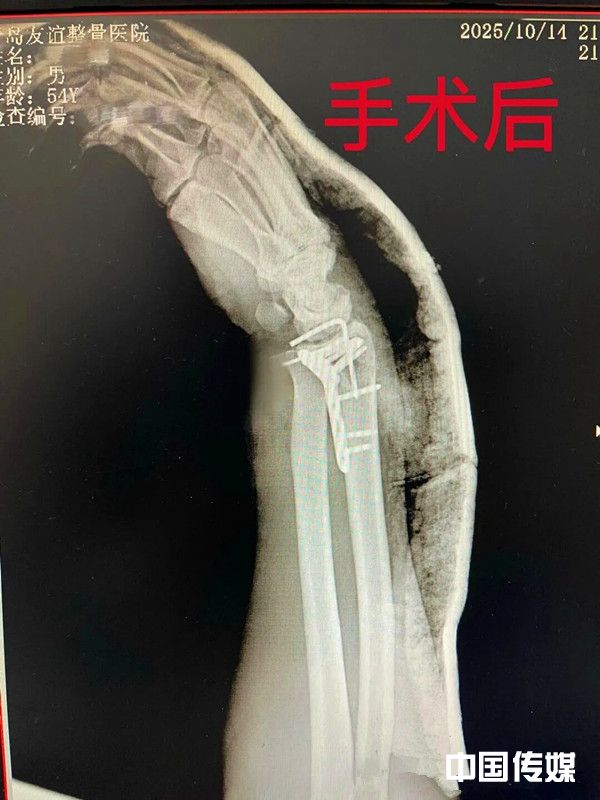

本网讯(记者万国栋通讯员万法玉报道)2025年10月14日中午,一场突如其来的意外,打破了山东平度市一位工友平静的生活。他的右腕部被机器完全切断,瞬间肿痛流血,情况万分危急!

腕部结构复杂,神经、血管、肌腱密布,再植手术无异于在显微镜下“重建一个世界”。该院的手术团队,凭借着丰富的显微外科经验和沉稳的匠心,在无影灯下开始了这场长达12个多小时的精细马拉松。

清创、骨折固定、肌腱缝合……最关键的一步,是在高倍显微镜下,将一根根比头发丝还细的血管与神经精准吻合。这是对医生技术、耐心和体力的终极考验。汗水浸透了手术衣,但所有人的目光都无比坚定:必须为患者接上这只手,保住他未来的生活和希望!

当最后一针缝合完成,止血带松开的那一刻,手术室里所有人都在屏息凝视——再植的右手颜色逐渐转为红润,血运恢复良好!